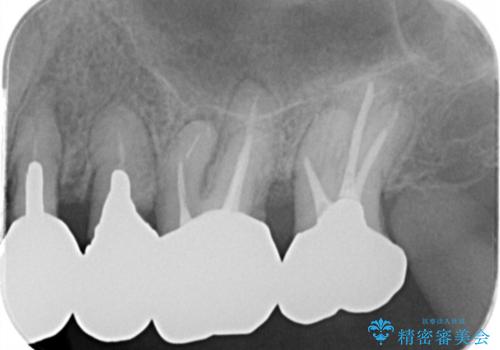

銀歯を除去したのち、虫歯を丁寧に除去し、歯を残せるのかどうかをしっかりと評価し、長期的な予後を見据えた虫歯治療を行っていきます。

銀歯の下で虫歯が再発していた歯は、無理に残しても割れてしまう可能性が非常に高いと考えたため、相談の上抜去を行いインプラント治療を行っていくこととしました。